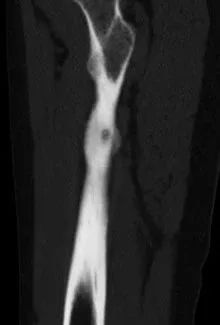

小陆右腿检查片

此为横切面视角

术中,影像引导射频穿刺